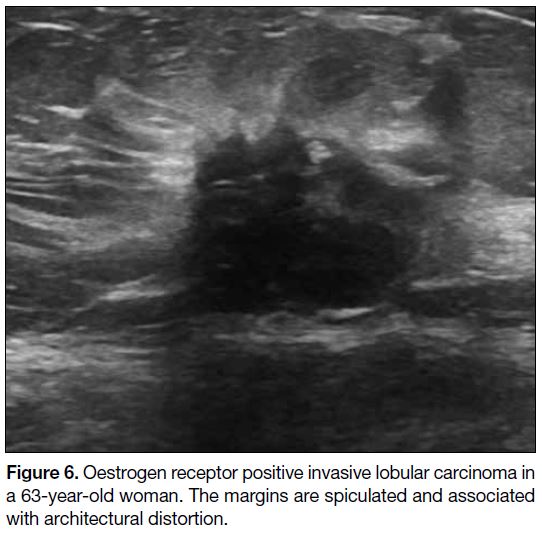

Previous meta-analyses[19] have shown that TNBC lacks

the typical malignant sonographic features of breast

cancer, including features of irregular shape, non-circumscribed

margin, non-parallel orientation, posterior

acoustic shadowing, and microcalcification (Figures 6 7 8).

Figure 6. Oestrogen receptor positive invasive lobular carcinoma in

a 63-year-old woman. The margins are spiculated and associated

with architectural distortion.